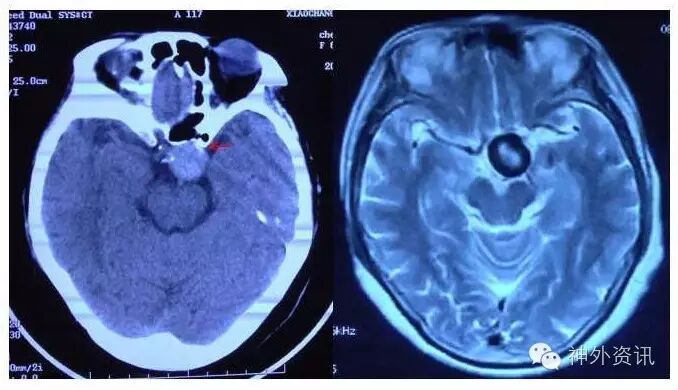

《后交通大动脉瘤》

《床突上段大动脉瘤》